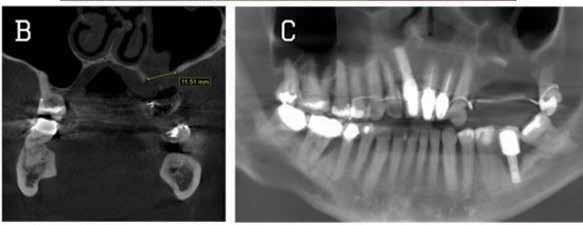

The newly formed Orofacial MRI Center (OMRIC, dentistry.umn.edu/omric) at the University of Minnesota School of Dentistry is home to the first dental-dedicated MRI (ddMRI) unit in North America and the second installation of its kind in the world. Researchers Drs. Don Nixdorf and Laurence Gaalaas have an extensive track record in dental MRI research and development. Still, they are thrilled to have as an imaging tool one of the very first dental-dedicated MRI units, a Siemens MAGNETOM Free.

Max Dental Edition* MRI scanner. In collaboration with Dentsply Sirona and Siemens Healthineers, Nixdorf and Gaalaas secured a multi-year research agreement and constructed a physical imaging center around a Free.Max MRI unit. Beginning in early 2025, they initiated research studies to investigate the utility of ddMRI diagnosis in patients with endodontic, orthodontic and TMJ conditions. Such work will establish the utility of an experimental dedicated extraoral dental MRI coil and support proven indications for ddMRI imaging in endodontic, orthodontic, TMJ and other dental patient populations.

Proton density (left) and CBCT (right) images of apical lesion and furcation involvement at tooth #2. This tooth was clinically diagnosed with pulpal necrosis and a crack involving the furcation.

Proton density image showing improved image detail provided by dental dedicated MRI coil.